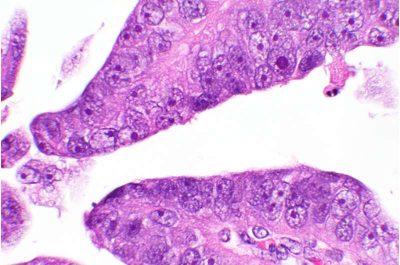

Cancro dell’endometrio-immagine: immagine microscopica di carcinoma sieroso papillare uterino, un sottotipo aggressivo di cancro endometriale. Crediti: Laboratorio Neda Moatamed/Sanaz Memarzadeh

Il cancro dell’endometrio è il tumore ginecologico più comune negli Stati Uniti ed è uno dei pochi tumori per i quali i tassi di sopravvivenza sono diminuiti costantemente negli ultimi decenni. I sottotipi più aggressivi sono un fattore determinante in questa tendenza: il carcinoma sieroso papillare dell’utero rappresenta solo il 10% delle diagnosi, ma quasi il 40% dei decessi.

Test più approfonditi su campioni tumorali di pazienti e su linee cellulari tumorali derivate da pazienti hanno confermato la superiore capacità della terapia di eliminare le cellule tumorali in sottotipi aggressivi di cancro endometriale, come il carcinoma sieroso papillare uterino.